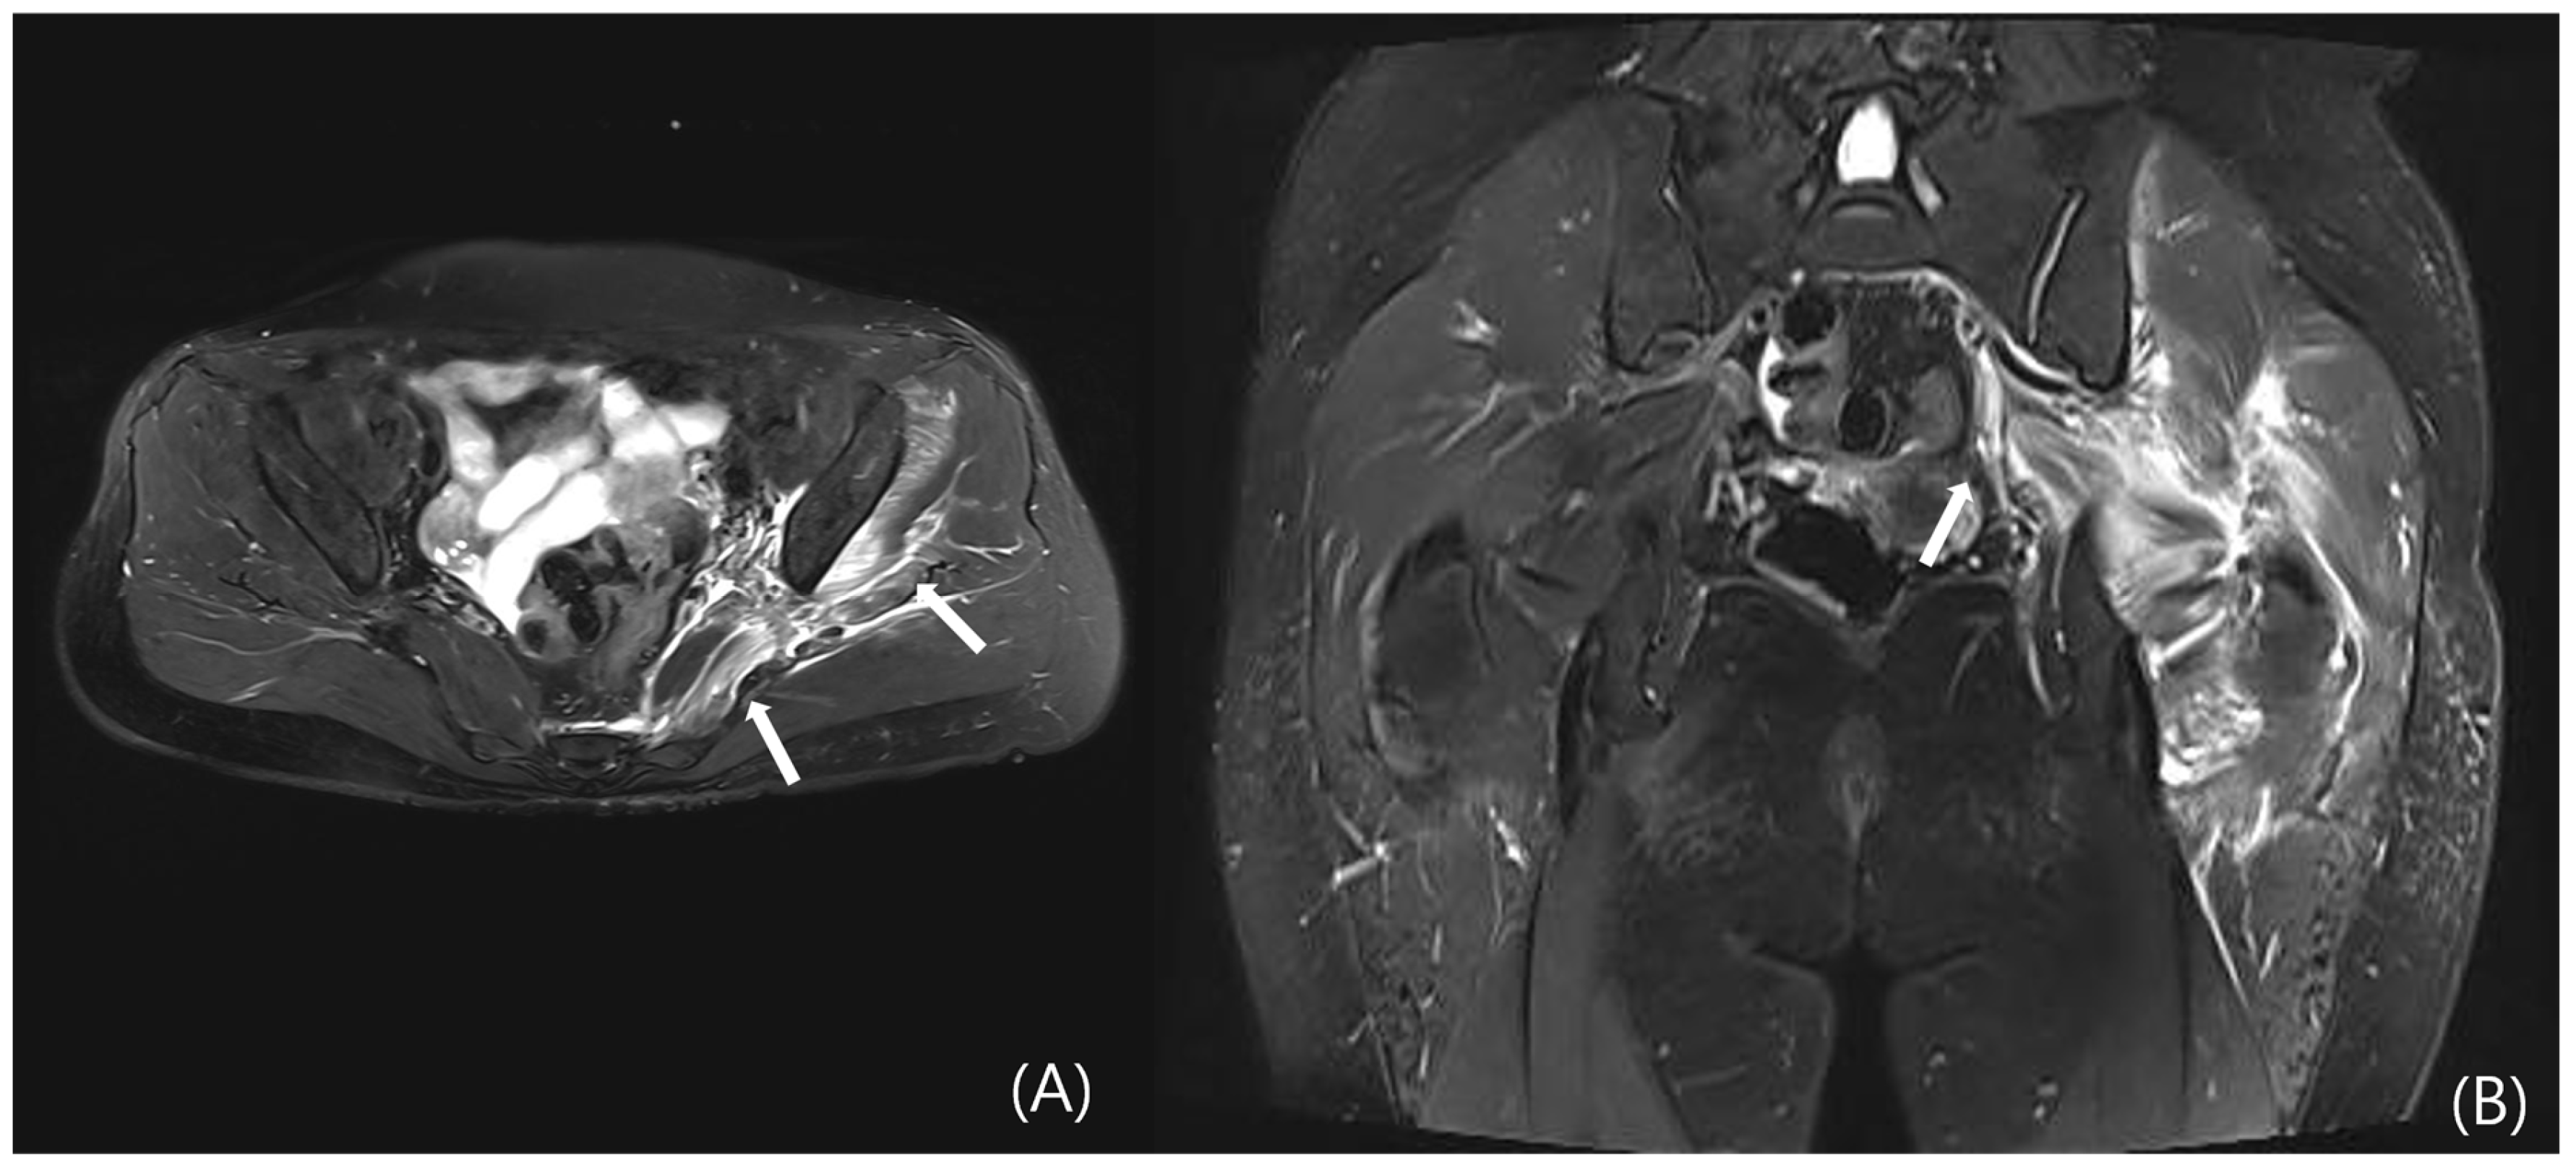

However, DGS may also result from intrinsic muscular or tendinous pathologies within the deep gluteal space. Tendon and muscle abnormalities can be evaluated by identifying peritendinous fat plane loss on T1-weighted images and increased intratendinous signal intensity and peritendinous edema on T2-weighted sequences. Tendon thickening and partial tearing may also be observed (Figure 5) [19]. Representative examples include quadratus femoris abnormalities due to ischiofemoral impingement (Figure 6) and proximal hamstring tendinopathy. Nevertheless, due to the anatomical depth and overlapping with adjacent structures, lesions involving the deep external rotators—including the piriformis, gemelli, obturator internus/externus, and quadratus femoris—are often difficult to visualize on MRI, posing diagnostic limitations.

Figure 6. Pelvic MRI of a patient who presented with right posterior hip pain and radiating pain to the right thigh, which had developed five months prior to admission. The patient reported characteristic worsening of pain after walking for more than 20 min. (A) Axial and (B) coronal T2-weighted images demonstrate edema of the right quadratus femoris muscle, associated with narrowing of the ischiofemoral (IF) space (white arrows).